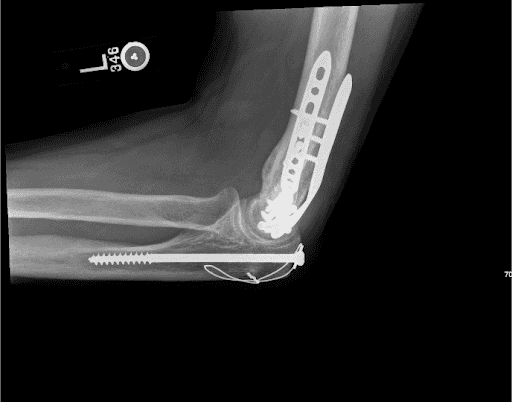

Imaging is essential to assess the integrity of the ORIF construct. Radiographs are done with lateral and slightly modified anteroposterior (AP) views. The AP view involves flexion of the elbow to about 40 degrees to allow the olecranon to move out of the way, allowing the distal humerus to be better visualized.6 There has been increasing interest in the use of computed tomography (CT) scans, particularly 3D reconstructions when there is articular involvement.11

Removal of the medial plate may not always be necessary; however, we felt that in this case the medial plate was quite prominent so its removal in the context of a healed fracture would help to relieve some of the patient’s symptoms. Pre-op x-rays are included The creation of an adipofascial sleeve around the transposed nerve we believe helps the nerve glide easily as the patient moves the upper limb and prevents recurrent nerve compression from scarring and fibrosis. The technique, in brief, is thus described here. A posteromedial incision is made over the medial epicondyle and extended 8–10 cm proximally and 4–5 cm distally. The ulnar nerve is identified proximally, just posterior to the medial intermuscular septum, after careful blunt dissection. It is then further dissected in an antegrade fashion taking care to keep the vascular supply of the epineurium intact. After the nerve is mobilized and transposed anteriorly, attention is turned to the adipofascial flap. The flap, with vascular supply in place, is carefully wrapped posterior-to-anterior and sutured to create a tunnel that surrounds the entire nerve length. Finally, ranging of the elbow is done to ensure the nerve is not kinked. This technique has been well-described in the literature with specific application in cases like this one.12–14

Figure 2. Lateral view of the Left elbow x-ray showing the position of the plates pre-op.